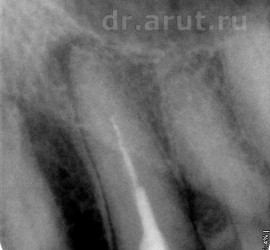

Аномалии строения и пороки развития зубов Пороки тканей зуба многообразны, они могут проявляться изолированно и сочетаться с аномалиями строения и пороками развития органов и систем всего детского организма, в том числе челюстно-лицевой области. Ткани зуба имеют эктодермальное (эмаль) и мезодермальное (дентин, пульпа, цемент) происхождение. В связи с этим пороки эмали […]